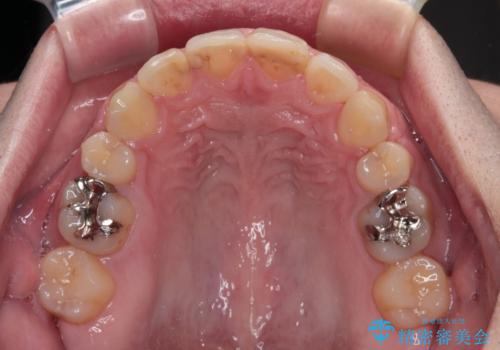

舌突出癖の改善トレーニングは、仕上がり、治療期間、そして治療後の後戻りに大きな影響を及ぼします。

トレーニングをしっかりと行っていただいたため、スッキリとした口元に仕上がりました。